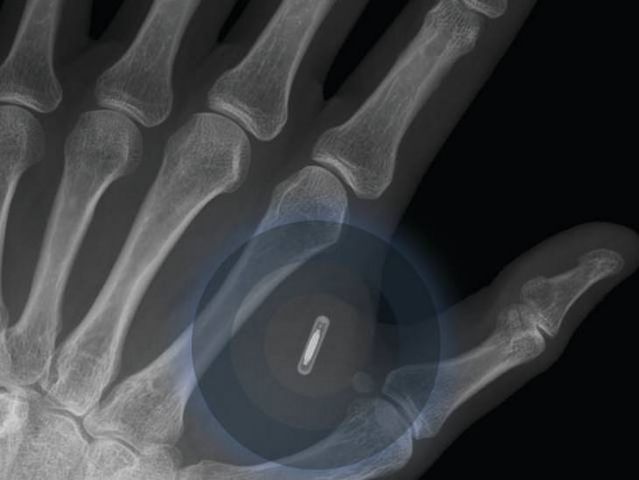

• Telefonía móvil "implantada"

Telefonía móvil "implantada"

La idea aquí es que un teléfono móvil pronto podrá controlar tu salud y signos vitales, estando permanentemente implantado en tu interior. Lo que es más, estos dispositivos llegarán incluso a interpretar nuestros pensamientos y transmitirlos a otro usuarios. Todo esto llegará en los próximos años..